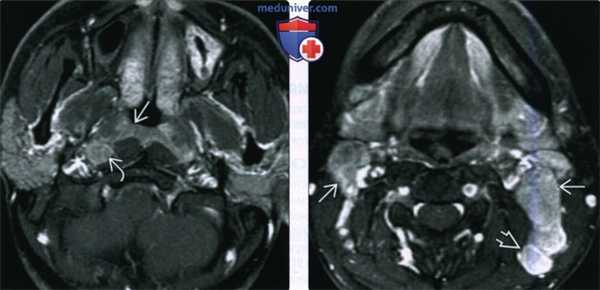

(Слева) При МРТ Т1 C+FS в аксиальной проекции, выполненной мужчине 26 лет из Азии с объемными образованиями шеи, определяется минимально асимметричный мягкотканный компонент в слизистой оболочке носоглотки, признаков инфильтрации превертебральных мышц не выявлено. Отчетливо визуализируется увеличенный заглоточный лимфоузел.

(Справа) При МРТ Т1 С+ FS в аксиальной проекции у этого же пациента визуализируются увеличенные лимфоузлы второго и пятого уровня, в которых были обнаружены метастазы недифференцированного некератинизирующего рака (третья стадия, T1N2), сочетанного с вирусной инфекцией Эпштейна-Барр.2. КТ при раке носоглотки:

(Слева) При МРТ Т1ВИ в корональной проекции в верхних боковых отделах носоглотки В визуализируется объемное образование с гипоинтенсивным сигналом, инфильтрирующее скат и левое окологлоточное пространство. Была выполнена эндоскопическая биопсия, подтвердился некератинизирующий рак носоглотки.

(Справа) При МРТ Т1 С+ FS в аксиальной проекции у этого же пациента в левом боковом кармане носоглотки визуализируется объемное образование (рак), распространяющееся в окологлоточное пространство. Хорошо видны вторично измененные контрлатеральные заглоточные лимфоузлы и ипсилатеральные (уровень ИВ) лимфоузлы (третья стадия, T3N2).в) Дифференциальная диагностика рака носоглотки: